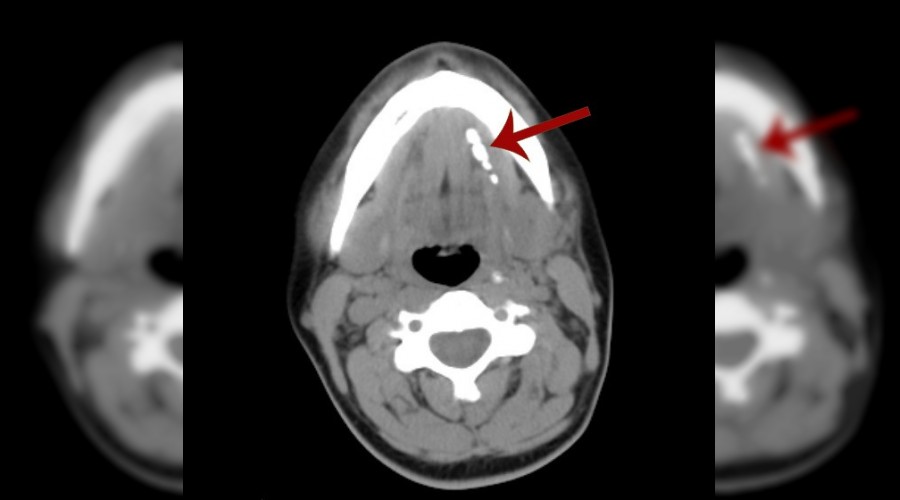

Mersin'in Tarsus ilçesinde yaşayan 34 yaşındaki ev hanımı Özlem Gül, uzun süredir çenesinin altında hissettiği ve 'boğaz enfeksiyonu'ndan kaynaklandığını sandığı ağrı için hastaneye gidince büyük bir şaşkınlık yaşadı. Ultrasound incelemesi yapan doktorlar, kadının tükürük bezinde 4 taş olduğunu belirledi. İkisi 8 mm, ikisi ise 2 mm büyüklüğündeki taşlar, mikrocerrahi yöntemiyle, ağız içinden girilerek ve mikroskop altında yapılan ameliyatla alındı.

Evli ve 1 çocuk annesi olan Özlem Gül, 3 yıldır sol çene altında hissettiği ağrıyı, sık sık yaşadığı boğaz enfeksiyonlarından kaynaklandığını düşündüğü için önemsemedi. Temmuz ayında ağrıların iyice artması ve çene altında şişkinlik oluşması üzerine bir kamu hastanesine gitti. Ultrasound ile inceleme yapan doktor, Özlem Gül'ün tükürük bezinde 2'si nohut büyüklüğünde olmak üzere 4 taş bulunduğunu söyledi. Duyduğuna inanmakta güçlük çeken Gül, aynı günlerde bir ziyaret için gittiği Ankara'da da bir başka kamu hastanesinde muayene oldu. Ankara'daki doktor da aynı bilgiyi verip, taşların ameliyatla alınması gerektiğini söyledi.

Ameliyat olmaya karar veren Özlem Gül, Medical Park Tarsus Hastanesi'ne gitti. Hastayı muayene eden Kulak Burun Boğaz Hastalıkları Uzmanı Op. Dr. Ali Kahlıoğulları, ameliyatın çene altından girilerek yapılması halinde komplikasyon riskinin olabileceğini ve tükürük bezinin zarar görme riski bulunduğunu belirterek, ağız içinden girilmesi yoluyla operasyonu yapmayı önerdi. Özlem Gül'ün kabul etmesi üzerine Op. Dr. Kahlıoğulları ve ekibi, mikrocerrahi tekniğiyle ve mikroskop altında operasyonu gerçekleştirdi. Ameliyatta, tükürük bezinden ikisi 8 mm çapında, ikisi ise 2 mm çapında olmak üzere toplam 4 taş çıkarıldı. Tükürük bezi ise ameliyattan zarar görmedi.

Son zamanlarda geliştirilen siyaloskopi yöntemiyle küçük taşlar kanal içinden alınabilmektedir. Fakat hastamız bu tekniğe uygun bir hasta değildi. Tükürük beziyle birlikte taşların alınması uygun olabilecek tedavi yöntemiydi. Ancak biz tükürük bezini korumak amacıyla mikrocerrahi ile ağız içinden taşları almayı planladık. Kısa süren bir operasyon ile taşlar alınarak tükürük bezi korundu. Hastamız operasyondan birkaç saat sonra sağlıklı bir şekilde taburcu edildi."